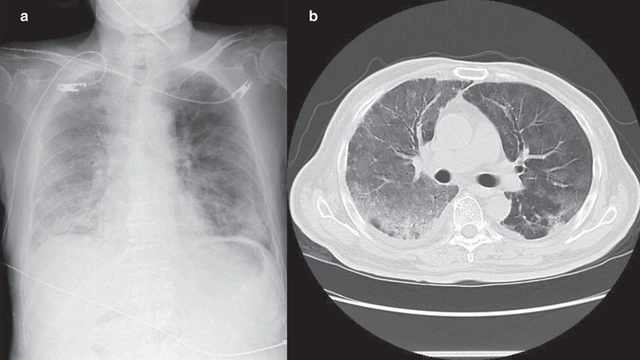

Viêm phổi kẽ sau Covid là biến chứng hô hấp kéo dài xảy ra sau khi mắc Covid-19. Trong bài viết này, bạn cùng tìm hiểu về nguyên nhân, triệu chứng, cách điều trị bệnh viêm phổi kẽ sau Covid.